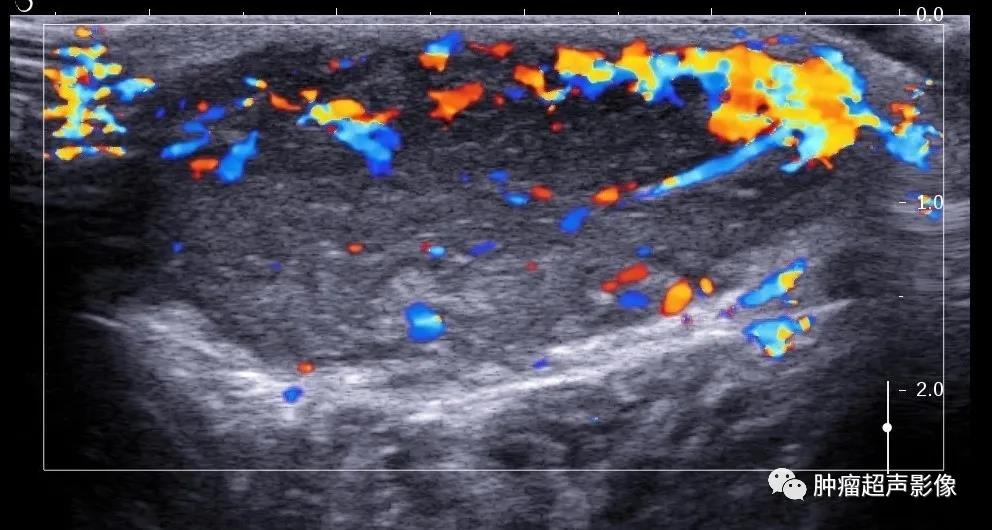

病理证实的隆突性皮肤纤维肉瘤:上臂隆起于皮肤表面的无痛肿块,呈紫红色,椭圆形,水平方向生长,内回声不均(见不规则条带状高回声),边缘可见伪足状低回声伸入高回声脂肪内,血流丰富。